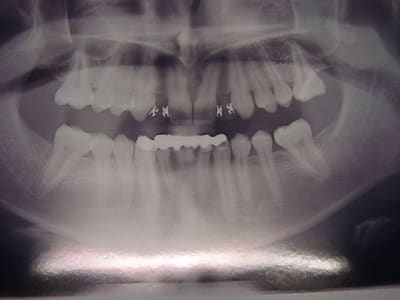

préparations pour bridge collé ...des commentaires?

tu fais un léger retour vestibulaire en mésial des canines, tu ne crains pas que ça devienne visible?

sinon occlusion? et ça parait bien.

pas vraiment de retour mais je souhaitais modifier légèrement l'aspect morpho des canines,

l'occlusion était un peu serrée au niveau des centrales ,mais il y a agénésie des 41 et 31 et j'ai remodelé le bridge collée antagoniste provisoire.

La 13 semble avoir une limite trop vestibulaire en effet...faudra voir le collage final...